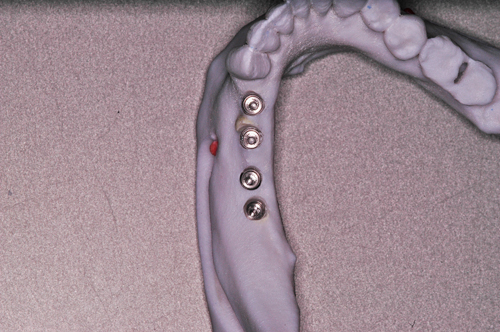

Palabras Clave: ELG: Estereolitográfico OH: Oclusión Habitual ORC: Oclusión en Relación Céntrica Paciente de 35 años de edad ,sexo masculino que lo derivan para implantar el tercer cuadrante. A la auscultación presenta ruidos articulares de tipo chasquido que remiten temporalmente luego de limitación de apertura bucal y maniobras quinesiológicas distractoras. También se observan recidivas de caries en algunos empastes y falta de disclusión canina de ambos lados. Se estudia el caso desde un punto de vista clínico, scanografico mediante Dentascan y tridimensional mediante montaje en articulador. A partir del scanner se obtienen datos para confeccionar modelo estereolitográfico (ELG),operar en el y construir férula quirúrgica dento-muco soportada. Habitualmente se procede directamente a implantar, dado que ese era el requerimiento del profesional derivante y el deseo del enfermo. Sin embargo, esa actitud enmascararía otro tipo de problemas que la boca presenta. Se consulta al odontólogo derivante, y coincide con mi opinión acerca de que si solo se lo implanta, sin corregir la posición mandibular, la situación de las ATMs, los empastes sin anatomía y la falta de disclusiones, el resultado final no será el deseado y su eficacia masticatoria no funcionará optimamente. Consultado el paciente coincide y acepta ese concepto y entonces procedemos a confeccionar un Jig de Lucia a partir del montaje de estudio, y lo dejamos puesto en boca toda la noche anterior a la consulta, para proceder a realizar un ajuste oclusal al día siguiente sin engramas anteriores, lo que facilita no tener que relajar nuevamente con laminillas de Long. En esta etapa pierde el implante correspondiente a la pieza 4.7 que traía en boca. Estabilizado el sistema, procedemos a la parte quirúrgica, comenzando por instalar la férula, retirar opérculos gingivales mediante bisturí circular, fresado óseo e instalación de implantes ,toma de impresión a cubeta fenestrada (pegando con metacrilato sin cambios dimensionales, los transfers a la cubeta especialmente diseñada.(1º método de pasividad protética utilizado), e instalación de tornillos de cicatrización. Inmediatamente de retirada la cubeta de boca y colocadas las réplicas de los implantes, procedemos a ferulizar los “ápices” de las réplicas para que no sufran movimientos durante el llenado de la impresión.(2º método de pasividad protética utilizado). Controlamos radiograficamente Tres meses después, procedemos a tomar nuevos registros de arco facial, registros intermaxilares en Oclusión en Relación céntrica, montaje de los modelos obtenidos intra operatoriamente y confección de un conjunto de cuatro coronas provisionales de metacrilato en el sector implantado y las correspondientes al maxilar superior. Verificada la perfecta función de todos los componentes, ausencia de todo tipo de síntoma y comprobada la paz en todo el sistema, procedemos tiempo después a confeccionar las fundas definitivas, que constituyen el “cerrojo” de la dinámica del mismo. Por último, corroboramos la oclusión fundamentalmente en lo que hace a la: